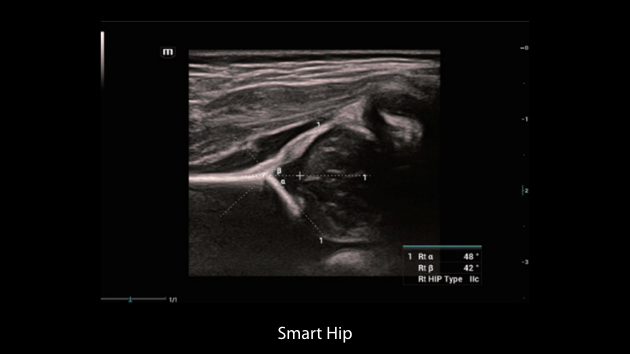

De Nuewa I9, speciaal ontworpen voor vrouwen en neonatale gezondheidszorg, biedt een innovatieve ervaring van binnenuit. Deze innovaties zijn ontwikkeld op basis van diepgaande inzichten in complexe klinische scenario's en bieden nauwkeurige en tijdige antwoorden, evenals een uitstekende effici?ntie en opmerkelijke gebruikerservaring.